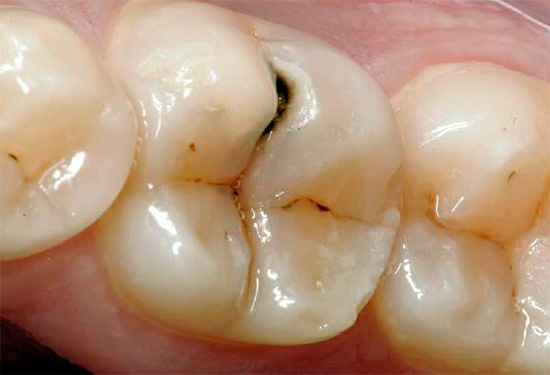

L'ispezione visiva dei denti è il modo principale per identificare una situazione cariogena nella cavità orale. La carie è caratterizzata dal fatto che in quasi tutte le fasi del suo corso, cambia il colore dello smalto dei denti. Anche nella fase spot, quando la dentina non è ancora interessata, lo smalto cessa di essere liscio e lucido e il dentista attento nota facilmente un tale cambiamento.

In fasi successive, determinare la carie con un semplice esame è ancora più semplice: porta alla comparsa di punti neri e marrone scuro sui denti o quando la dentina è danneggiata, sotto lo smalto sono visibili cavità scure.

Non sorprende, nella maggior parte dei casi, la diagnosi visiva della carie dentale può rivelare la maggior parte delle aree interessate. Con lei, il dentista esamina attentamente i denti da diversi lati con uno specchio. Inoltre, il medico può eseguire una sonda sonda: in luoghi dello sviluppo precoce del processo cariato, si avverte chiaramente la rugosità della superficie dello smalto.

È la diagnosi visiva più disponibile a casa e ti consente di riconoscere tu stesso la patologia dei denti. Basta solo esaminare attentamente i denti allo specchio. Vale la pena non solo cercare aree francamente nere, ma anche prestare attenzione a tutti i luoghi che si stagliano sullo sfondo di denti bianchi puri. Ricorda: le aree nere e marroni indicano un danno sufficientemente profondo al dente (nel migliore dei casi, solo lo smalto sarà pigmentato). Un tale dente dovrà probabilmente essere forato, forse anche un nervo verrà rimosso da esso. Pertanto, il dentista dovrebbe essere consultato anche prima della comparsa di un danno visibile significativo.